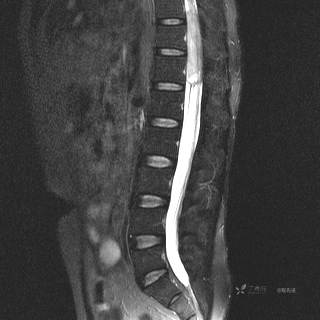

MR

T2压脂